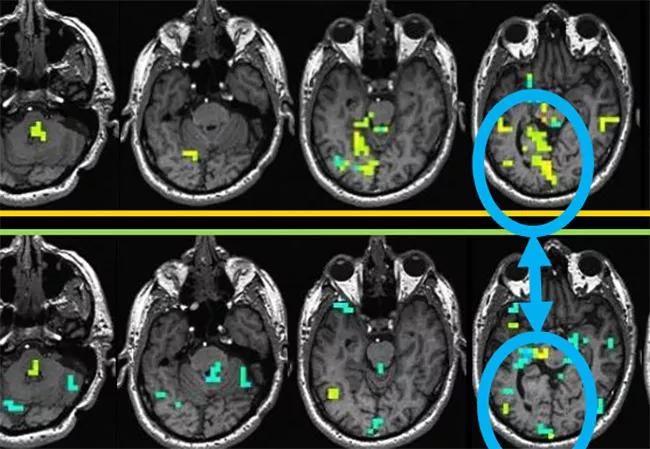

To date, seven patients have been studied and there have been no adverse reactions. Various stimulation parameters were explored, generally showing robust BOLD activation with voltages greater than 5V. BOLD activation included brain regions both proximal and distal to the electrodes, with patterns reflecting motor circuits, and the patterns were very sensitive to lead location. The figure presents example findings.

Figure. The top row of images shows BOLD activation maps resulting from stimulation of electrode contacts in the globus pallidus interna (GPi) regions. This stimulation, depicted in the large image on the lower left, is specifically a bipolar stimulation between contacts 0 and 1, where the red spheres in the lower left image indicate predicted regions depolarized by electrical current. Yellow-green shading indicates regions with increased BOLD activation with electrical stimulation, whereas blue regions show decreased activation with electrical stimulation. The second row of brain maps shows the results when the location of the stimulation electrodes is slightly changed, now in the adjacent contact pair 1-2. While the two rows of brain maps show activation in many brain regions, there are some notable differences, such as the right-sided visual areas of the occipital lobes, as indicated within the blue circles (fourth images in each row). This is likely due to proximity of the activation at contacts 0-1 to the optic tracts, as indicated by the arrow.